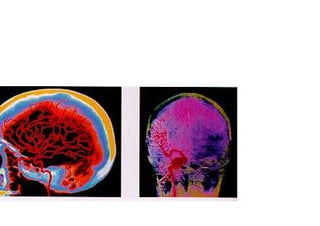

Como área fundamental del conocimiento, tiene un

interés particular en el análisis de la organización

nerviosa de los procesos psicológicos.

del sistema nervioso, toda la actividad psicológica.

Como área clínica de trabajo, la evaluación

neuropsicológica consiste en una exploración

de los dominios cognoscitivos. Es decir, del

nivel de inteligencia general, de la memoria, (a

corto plazo, episódica y semántica), del

lenguaje (oral, leído y escrito), de las praxias,

de las gnosias, de las funciones ejecutivas, de la

atención, el cálculo y la orientación. Estos

dominios son explorados a partir de pruebas

específicas que van a permitir evaluar las

capacidades cognoscitivas de los pacientes y de

establecer el cuadro de capacidades preservadas

y comprometidas.